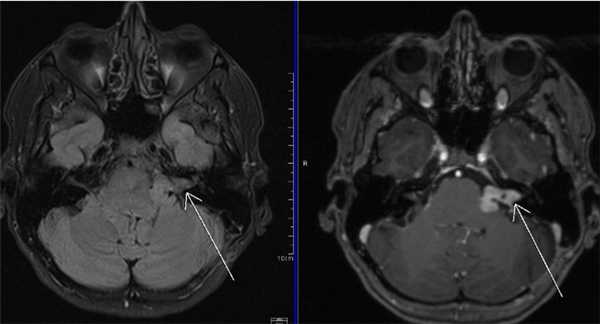

МРТ головного мозга. На мрт в аксиальной плоскости отмечается объемное образование внутреннего слухового прохода слева (стрелка), с четкими и неровными контурами, деформирующее окружающие структуры. После внутривенного введения парамагнитного контрастного вещества отмечается интенсивное и неоднородное его накопление образованием (изображение справа) — невринома.